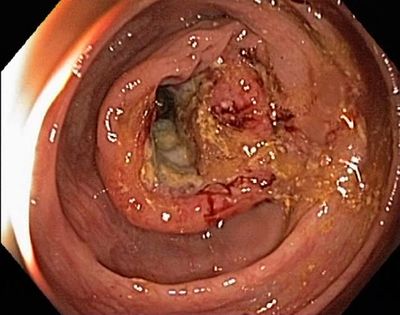

Kalın barsak sindirim sisteminde kanserin en sık görüldüğü bölgedir. Kalın barsak kanserleri aynı zamanda en sık görülen kanserlerden biridir.

Kalın barsak kanserlerinde görülen belirtiler ise barsak alışkanlıklarında değişiklikler, dışkıda kan, ishal/kabızlık, barsaklarda tam boşalamama hissi, kilo kaybı, yorgunluk, bulantı ve kusmadır. Tam tıkanma durumlarında ise gaz ve dışkı çıkaramama gibi belirtiler görülür.

Kolorektal kanserlerin çoğu adenomatöz poliplerden köken aldığından dolayı korunma premalign lezyonların tanımlanması ve çıkarılmasına dayanır. Sindirim sistemi şikayeti olan hastaların tümü özellikle kolonoskopi ile değerlendirilmelidir. Kolonun değerlendirilmesinde en etkin yöntem kolonoskopidir. 50 yaş üzerindeki herkese gaitada gizli kan testi yapılmalıdır. Diğer bir tanı yöntemi ise sanal kolonoskopidir (BT kolonografi).